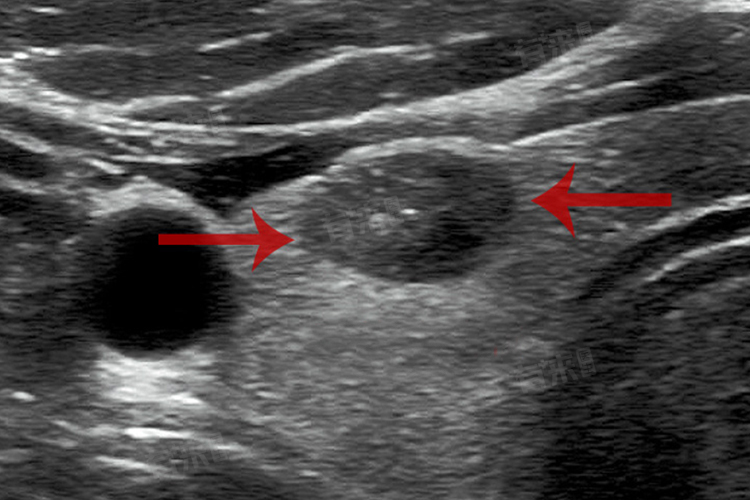

甲状腺结节点状强回声是指在进行甲状腺超声检查时,观察到甲状腺部位存在结节,并且结节内部的回声强度高于周围正常的甲状腺组织。

- 结节钙化:钙化是甲状腺结节中常见的超声表现,它可能由钙盐沉积形成。钙化可能是良性结节的特征,但也可能出现在少数恶性结节中。钙化灶在超声图像上表现为明亮的点状强回声。

- 结节血供丰富:在超声检查中,点状强回声结节的后方常常有较丰富的血流信号,这可能与结节内的血管异常扩张有关。血流供应的增加可能提示结节的恶性潜力较大,需要进一步评估和随访。

- 恶性结节:点状强回声也可能是恶性结节的表现,如甲状腺癌。恶性结节通常伴有其他异常表现,如结节形状不规则、边缘不清、血供丰富等。对于疑似恶性结节,需要进行进一步的检查,如穿刺活检或手术切除,以确定其性质并制定相应的治疗方案。